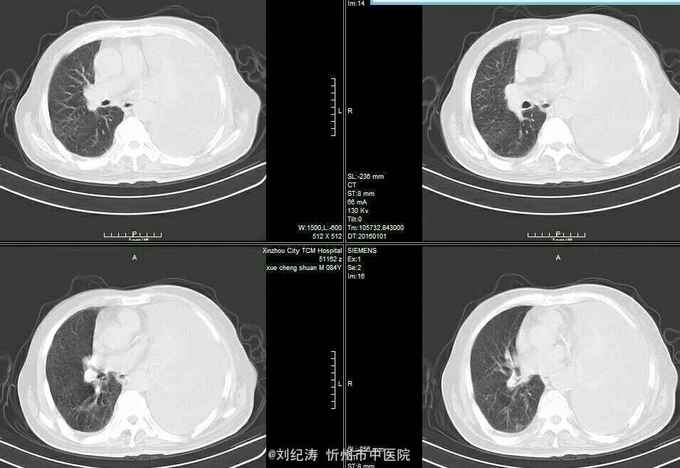

查体:ECOG评分:3分,生命指征平稳,浅表淋巴结未触及明显肿大,双眼睑无水肿,唇无发绀,颈软,双侧胸廓对称,左肺语颤增强,左肺呼吸音消失,右肺呼吸音粗,可闻及哮鸣音,心律齐,腹平软,肝脾肋下未触及,移动性浊音阴性,肠鸣音3次/分,双下肢无水肿。 辅助检查:血常规(2016.1.1):WBC:10.6*109/L,RBC:4.69*1012/L, PLT:165*109/L ,HGB:167g/L.生化(2016.1.1):谷丙转氨酶11U/L,谷草转氨酶11U/L,总蛋白60g/L,白蛋白33g/L,尿素:9.8mmol/L,肌酐:123umol/L,尿酸:251 umol/L,血糖:7.37 mmol/L;电解质:钾:4.79mmol/L,钠:123.5 mmol/L,氯:85.7 mmol/L,钙:2.03 mmol/L。肺部CT(2016.1.1):左肺完全萎缩,左侧胸腔大量积液,右肺未见异常,纵膈轻度右移,未见明显肿大淋巴结。